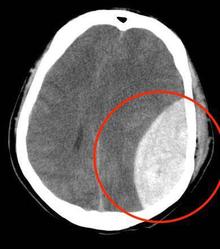

醫護人員證明 青年被港警打至腦出血 6小時後才送醫

2019-10-09 11:08:45香港有醫護人員透露,一名青年抗議,遭警方以警棍毆打頭部致顱內出血,拖延6小時後才送醫,如再延遲傷者恐成植物人,甚至可能死亡。